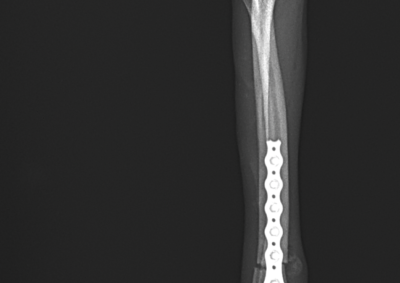

注意 ボタンをクリックした先に、治療中および手術中の画像が説明で使用されている場合がございます。 そのような画像に弱い方は閲覧なさらないようお願いいたします。 整形外科 若齢犬の橈骨固定術 #271 整形外科 前十字靭帯断裂(中型犬)に対するCBLO #255 整形外科 超小型犬に対する上腕骨遠位Y字骨折 整形外科 大型犬の前十字靭帯疾患(慢性経過)に対するCBLO #254 整形外科 橈骨固定術 #270 整形外科 膝蓋骨内方脱臼に対する人工滑車置換術 PGR #23 整形外科 犬の前十字靭帯(疾患)部分断裂に対するCBLO #253 整形外科 犬の前十字靭帯断裂に対するCBLO #252 整形外科 膝蓋骨内方脱臼+前十字靭帯断裂に対するPGR#22・LSS 整形外科 大腿骨骨折 整形外科 橈骨固定術 #269 整形外科 上腕骨外顆骨折の癒合不全 123456> 症例カテゴリー 放射線治療整形外科軟部組織外科脳神経外科内科腫瘍外科救急・集中治療リハビリテーション科腫瘍内科内視鏡科脳神経科呼吸器外科中医・漢方猫の腎移植循環器科